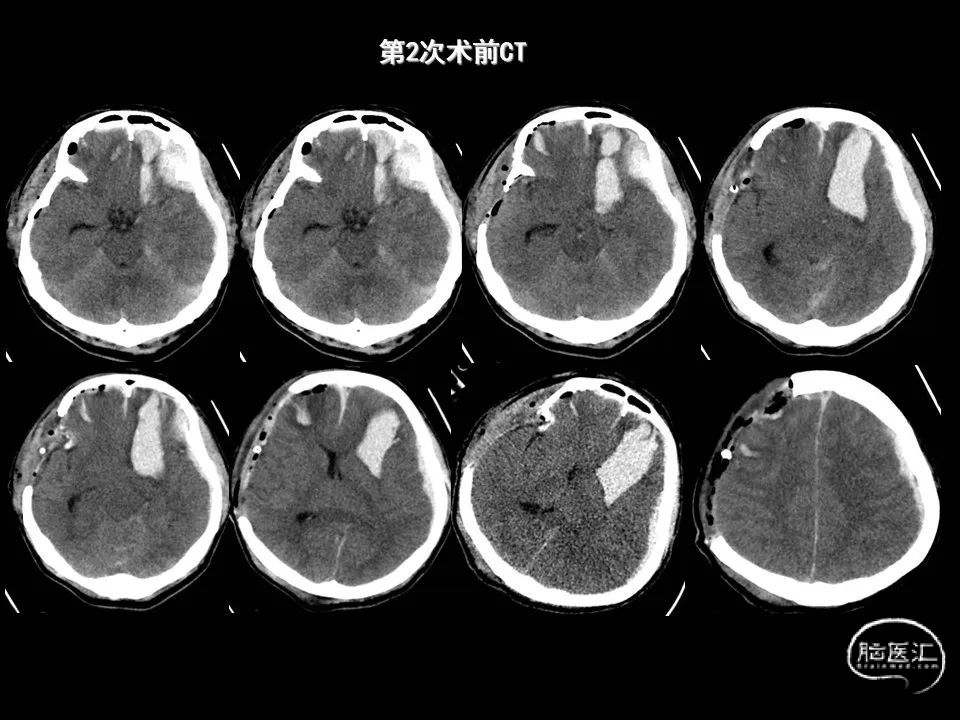

今天为大家分享的是《监测有道丨颅脑创伤-神经重症周刊》第338期,由海南省人民医院朱蔚林教授带来的:2例脑出血微创手术,欢迎阅读、分享。